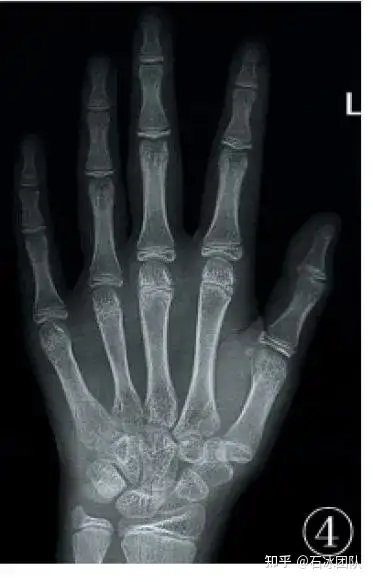

它引起与kallmann综合征的x连锁形式,并且与嗅觉丧失,双手同步和肾